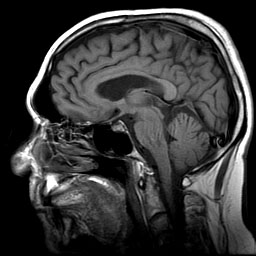

Using MRIs for snake venom gland observation

This is gonna be a bit different than usual posts cause it will be an amalgamation of a couple papers to piece it together for my own experiment with western hognose snakes. Evolution and diversification of the toxicofera reptile venom system- Fry et al., 2009– My experiment will be using western hognose snakes in variousContinue reading “Using MRIs for snake venom gland observation”